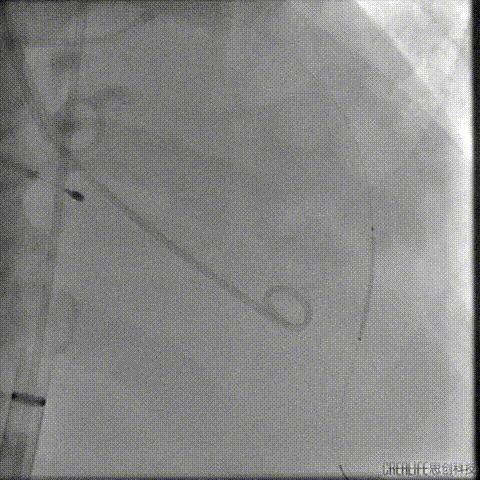

经瓣架网眼挂上指引管

反复确认指引管经瓣架网眼

指引管经瓣架网眼

经网眼置入导丝

置入4.0mm*23mm微创冠脉支架

定位并释放支架

退出球囊扩张突入瓣架部位

复查冠脉造影

多体位复查冠脉造影